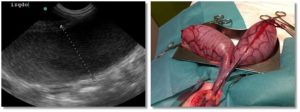

Esta es una sección realizada en colaboración de los compañeros veterinarios con los que trabaja DXIA, en la cual, compararemos imágenes reales, obtenidas durante la resolución quirúrgica, con imágenes ecográficas.

Una forma que puede ser interesante de colaboración y que nos ayuda a poder darle color a las imágenes obtenidas durante un estudio ecográfico seria comparar las imágenes reales que se obtienen durante las cirugías o intervenciones con las imágenes diagnósticas obtenidas durante el estudio ecográfico del paciente. Os quiero animar a todos a que mandéis dichas imágenes y a que este apartado crezca día a día.

En las imágenes publicadas en la web, por la ley de protección de datos, no se indicarán datos del paciente ni de la clínica y sólo se pondrán aquellas que la clínica o los compañeros veterinarios envíen para dicho fin.